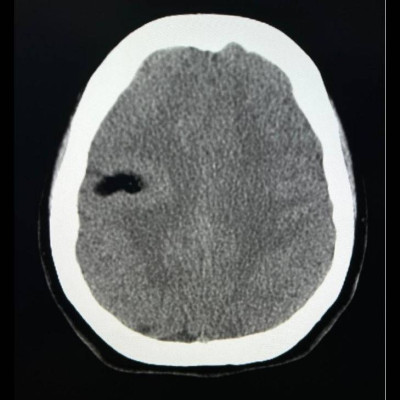

29 yaş, K

Baş ağrısı

Arteriyovenöz Malformasyon

AVM